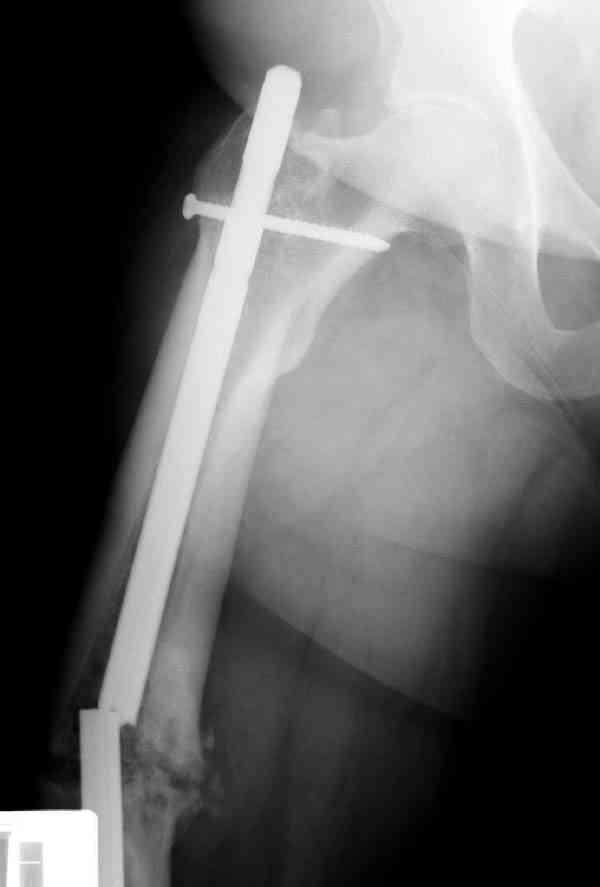

Уважаемые коллеги! У пациента 50-ти лет ложный сустав голени, перелом интрамедуллярного штифта. Перелому около 2 лет, ходить с полной нагрузкой начал через 3 мес. после операции. Боли при ходьбе почувствовал около 2 мес. назад. На данный момент ходит с полной нагрузкой без посторонней опоры. Среди коллег развернулась дискуссия по поводу способа оперативного лечения: -удаление штифта с перештифтовыванием блокированным штифтом с рассверливанием и остеотомией м\б кости -стабилизация зоны ложного сустава по медиальной поверхности LCP-пластиной с декортикацией или без -удаление штифта или без и синтез в АВФ с декотрикацией или без и остеотомией м\б кости

уважаемый коллега! Здесь имеется типичный тугой ложный сустав б/берцовой кости. У нас бы удалили старый стержень, реостеосинтез более толстым стержнем с рассверливанием с блокированием в динамическом варианте. Проблема будет с удалением дистального отломка стержня. Здесь на форуме это вопрос уже рассматривался неоднократно. Поищите по поисковику.Вот здесь, кажется http://weborto.net/forum/1164105478/, http://weborto.net/forum/1192794837

Сросшаяся малоберцовая как распорка привела к образованию ложного сустава. В таких случаях удаляем сломанный штифт и проводим стимуляцию ложного сустава рассверливанием. Рассверливание канала создает стимуляцию на месте ложного сустава, и динамический вариант блокировки штифта с большим диаметром создаст стабильность. Ранняя нагрузка после остеотомии малоберцовой приведет к сращению ложного сустава.